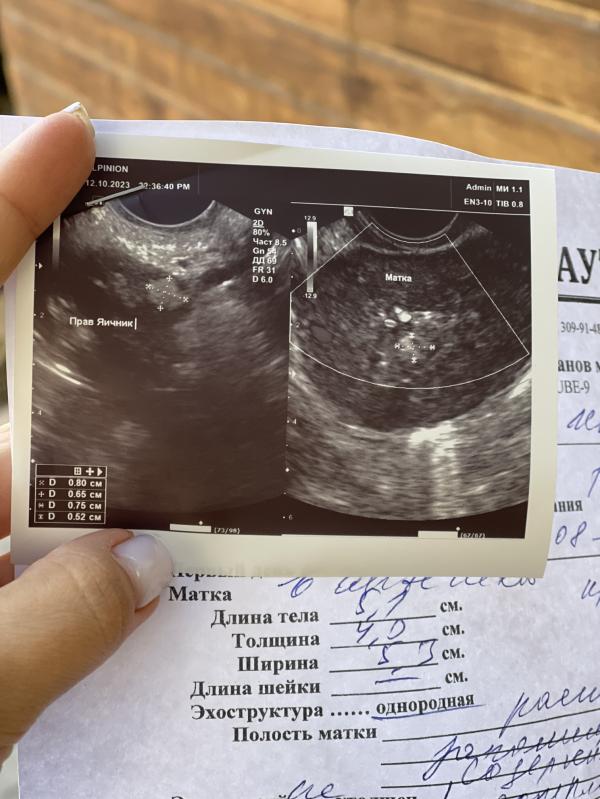

Третьи роды, сегодня уже 55дней прошло, оказывается там осталось ещё сгусток, как посоветуете ?! Сделать чистку или попробовать лекарства и окситоцин как гинеколог хочет попробовать, типа там мало и организ сам вытолкнет!

Но блин до этого что то резко (недели 3 назад) сгусток вышел, и я предполагаю что теперь сейчас остатки о того сгуска, но с одной стороны может вышло уже что вышла а этот крепко сидит, и не будет ли что и лекарства зря начну и ещё блин если не получится то по любому на чистку!